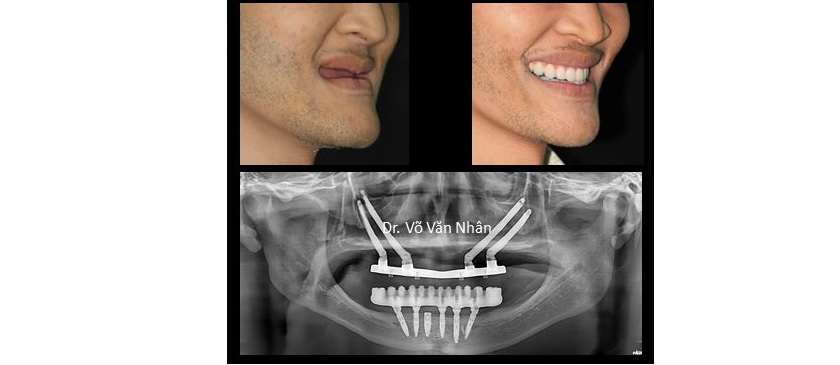

Tiến sĩ, Bác sĩ Võ Văn Nhân chia sẻ về tình trạng này: “Trường hợp của khách hàng Kim Huệ là vô cùng đặc biệt. Sau khi thăm khám lâm sàng và khảo sát trên phim X-quang 3 chiều cho thấy, xương hàm bị tiêu xương trầm trọng sát đáy xoang hàm, xương hàm dưới bị tiêu xương và lộ dây thần kinh. Để giải quyết trường hợp này chỉ còn một giải pháp khả thi là thực hiện song hành cả 2 kỹ thuật: dời dây thần kinh(*), cấy ghép implant để phục hồi hàm răng dưới(*) và cấy implant xương gò má để phục hồi hàm răng trên(*)”.

Sau 4 giờ phẫu thuật, Ts.Bs Võ Văn Nhân và ê kíp đã thực hiện thành công ca phẫu thuật cấy ghép răng cho khách hàng thiếu răng bẩm sinh(*). Sự thành công của ca phẫu thuật này do Ts.Bs Võ Văn Nhân thực hiện đã đánh dấu một bước tiến mới cho ngành implant nha khoa tại Việt Nam. Bên cạnh đó, Ts.Bs Nhân đã báo cáo kỹ thuật implant xương gò má cải tiến tại Hội nghị quốc tế 2015 - công trình này đã đóng góp lớn về mặt khoa học, góp phần hoàn thiện kỹ thuật này trên thế giới.